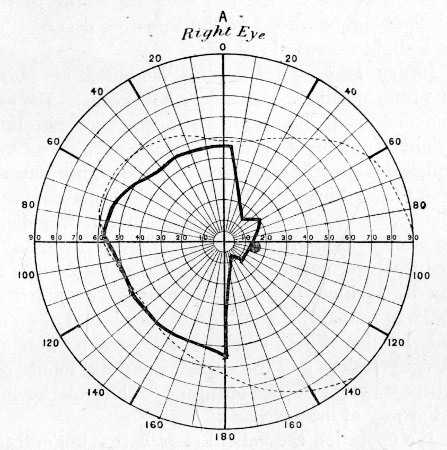

73. Visual Field in Occipital Injury 279

74. " " " 279